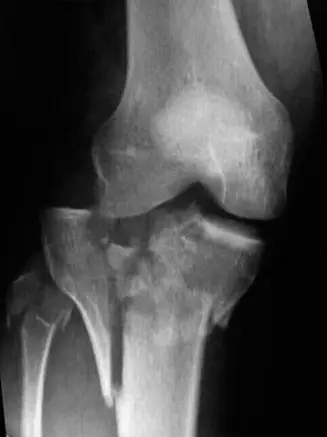

الأشعة السينية

• الاستخدام: هي الخطوة الأولى في التصوير. يتم التقاط صور للركبة المصابة من زوايا مختلفة (أمامية خلفية AP، جانبية Lateral، ومائلة Oblique).

• ماذا تظهر:

• المنظر الأمامي الخلفي (AP View): يكشف عن تفتت شديد في كلتا لقمتي الظنبوب (الداخلية والخارجية)، انخفاض في السطح المفصلي، واتساع في عرض الهضبة.

• المنظر الجانبي (Lateral View): يوضح الكسور متعددة الأجزاء التي تمتد إلى منطقة ما فوق المفصل (Metaphysis)، مع إزاحة خلفية لجزء كبير من الهضبة وانخفاض في السطح المفصلي.

• المناظر المائلة (Oblique Views): تساعد في تحديد مدى التفتت وتوجيه الشظايا، خاصة في الأجزاء الخلفية من اللقمتين.

• التصنيف الأولي: بناءً على الأشعة السينية، يمكن للأستاذ الدكتور محمد هطيف أن يشتبه في كسر هضبة الظنبوب من النوع السادس، الذي يتميز بانفصال الجزء المفصلي عن جسم العظم وتأثر كلتا اللقمتين.